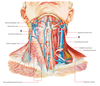

What are the 2 triangles of the neck?

Anterior and posterior triangles